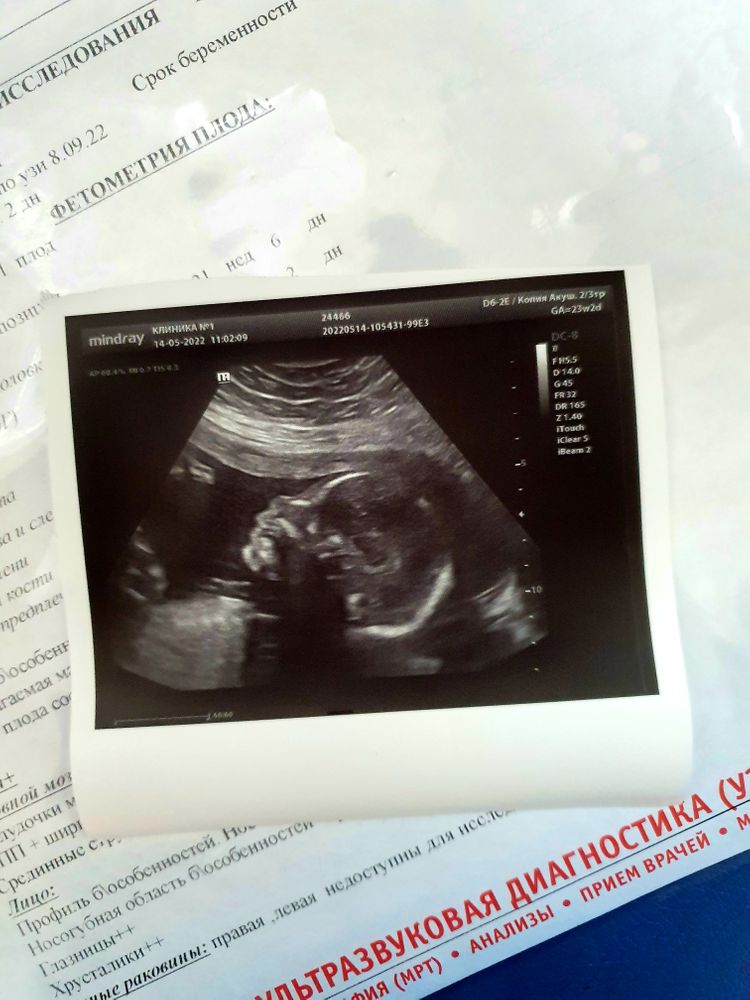

Были на узи,23+5

С малышом все хорошо,развит по сроку. Подтвердили мальчика☺️ На 2м скрининге в 19 недель поставили низкую плацентацию, сейчас плацента выше зева на 71 мм,т.е поднялась хорошо. А вот с рубцом от кс вопрос. В 19 недель он был очень тонкий, 1.8 мм,сейчас в 23 нед. он 3.5мм. Плацента, знаю,может подняться,а рубец может утолщиться? Но главное, что все хорошо и уже переживаний стало намного меньше😌